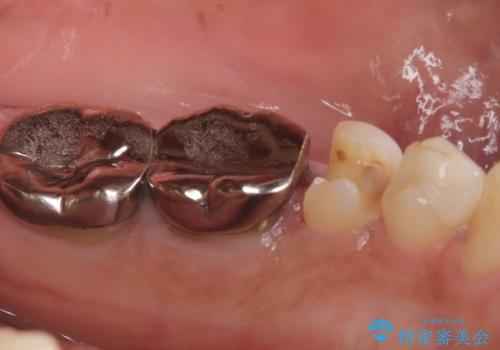

メタルインレーを除去したところ、二次カリエスうを確認したため除去・CR裏層の後、形成・印象しています。

セラミックインレーの接着操作時にはラバーダム防湿を行っています。